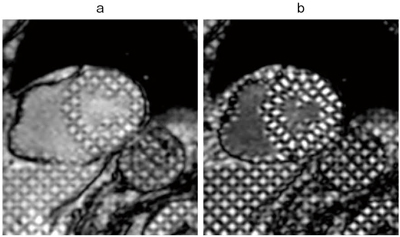

図1 タギング画像 |

心筋タギング法は、空間選択的なRF pulseにより心筋に標識(Tag)を付加することで、非侵襲的に心筋壁運動評価を可能にする方法である(図1)。このタギングMRIによる心筋運動評価は以前から行われていた方法だが、3.0T MRIを用いることで組織T1緩和が延長し、標識の持続時間が延びた。そのため収縮期まで標識が残り、観察がしやすくなった。ストレイン解析はこのデータを基に心筋の収縮を定量的に評価するものである。